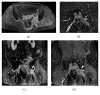

Magnetic resonance neurography is a high-resolution imaging technique that allows evaluating different neurological pathologies in correlation to clinical and the electrophysiological data. The aim of this article is to present a review on the anatomy of the lumbosacral plexus nerves, along with imaging protocols, interpretation pitfalls, and most common pathologies that should be recognized by the radiologist: traumatic, iatrogenic, entrapment, tumoral, infectious, and inflammatory conditions. An extensive series of clinical and imaging cases is presented to illustrate key-points throughout the article.